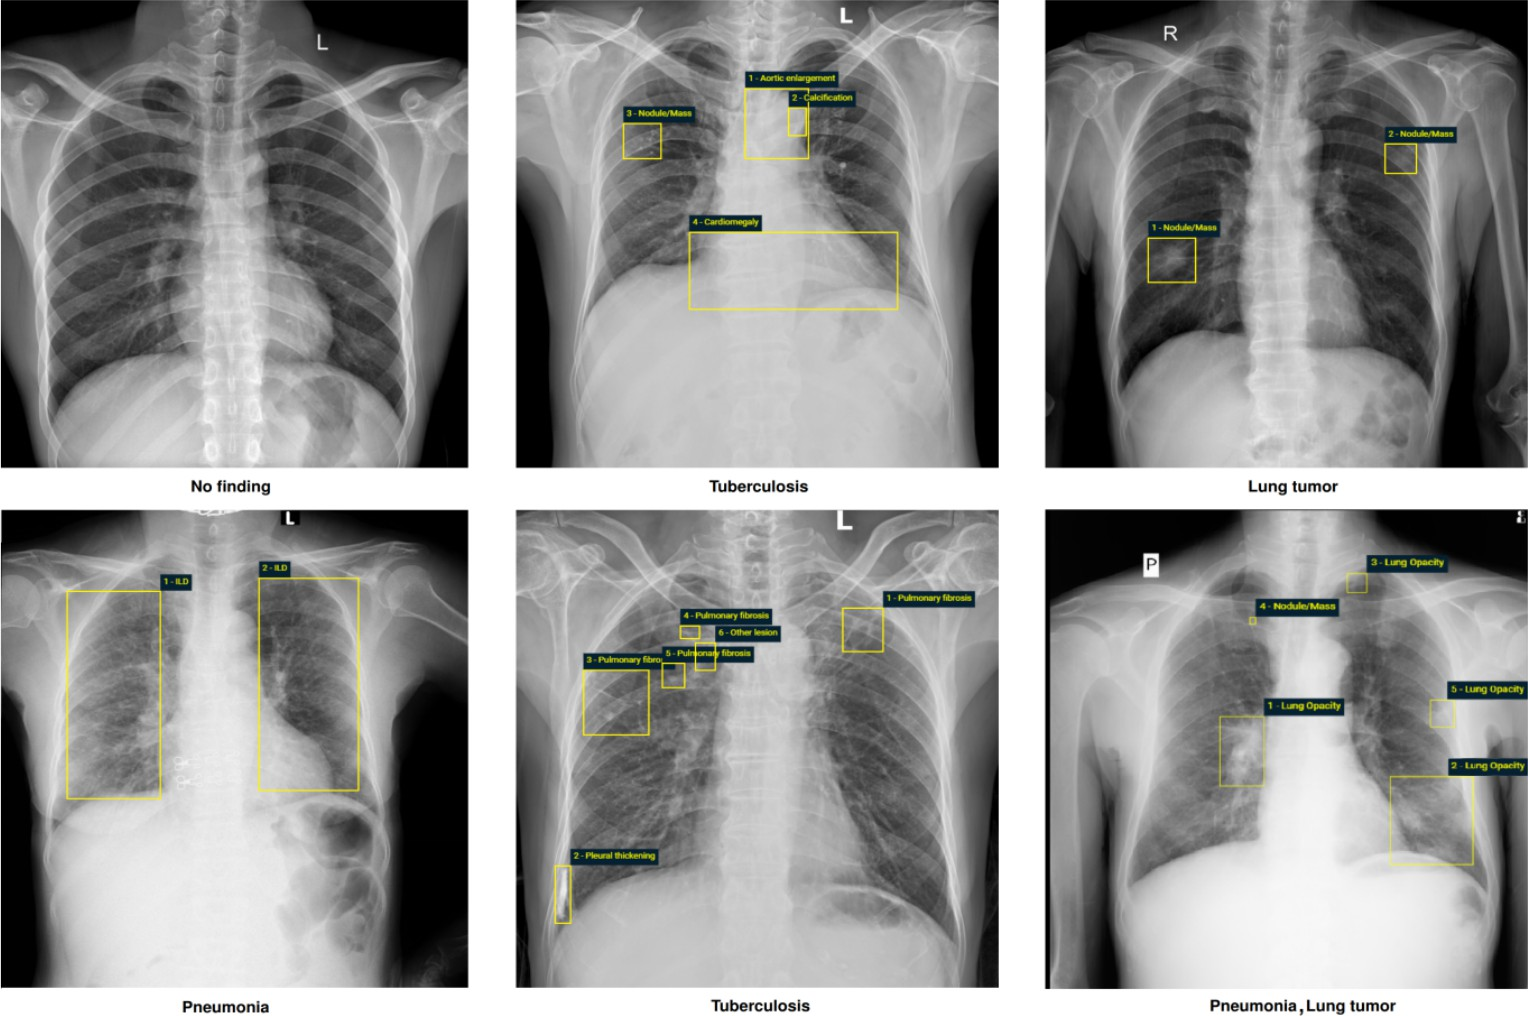

The VinDr-CXR dataset (nguyen2022vindr), which comprises posterior–anterior views of chest X-rays, was used to evaluate the proposed method. It includes a total of 18,000 images, divided into a training set of 15,000 images and a test set of 3,000 images. Each X-ray image corresponds to a different individual and is annotated with diagnoses provided independently by three radiologists. The diagnostic annotations consist of 22 local labels and 6 global labels, including a “no finding” label to indicate the absence of disease. Global labels refer to overall disease diagnoses assigned to the patient, while local labels represent specific abnormalities identified within the image. For each image, each radiologist indicated which global and local labels they would assign. In addition, bounding boxes were provided to localize each instance of a local abnormality on the X-ray. Figure 2 shows example images from the VinDr-CXR dataset, where global disease labels are listed at the bottom and local pathologies are highlighted with bounding boxes (nguyen2022vindr).

Refer to caption

Figure 2. Example chest X-ray images from the VinDr-CXR dataset (nguyen2022vindr), showing the detected diseases and the corresponding regions of interest within the images.